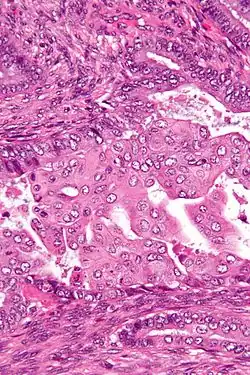

Micrograph of an atypical polypoid adenomyoma. H&E stain.

APAs are characterized by glands with abnormal shapes that: (1) often have squamous metaplasia, and (2) are surrounded by benign smooth muscle.[1] Nuclear atypia, if present, is mild.

The microscopic differential diagnosis includes endometrial carcinoma and endocervical adenocarcinoma.